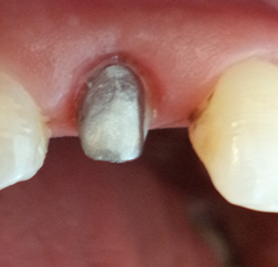

The tooth was prepared with a circumferential chamfer margin to provide adequate support for the zirconia crown. Care was taken to preserve as much tooth structure as possible while ensuring sufficient clearance for the prosthetic material. The preparation extended slightly subgingivally on the vestibular wall to manage the damaged area and achieve an optimal emergence profile (Figure 4).

Figure 4: Peripheral Tooth Preparation.